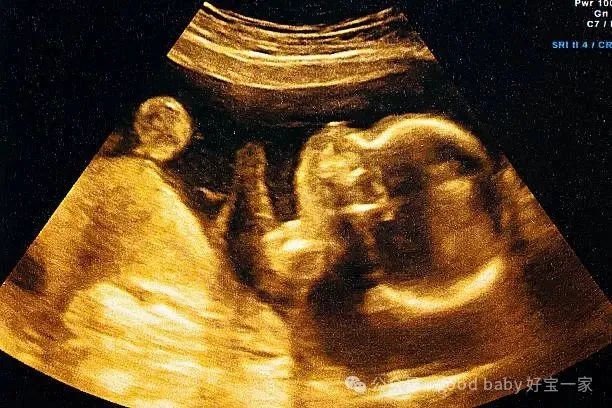

在辅助生殖领域,反复种植失败(RIF)像一座大山,横亘在求子家庭面前。它是指历经多次胚胎移植,都未能成功妊娠。据统计,约

在我国,试管婴儿的平均单次移植成功率约 40%,而反复种植失败的患者占比高达 30%。PGT-A 技术的出现,就像给胚胎戴上了